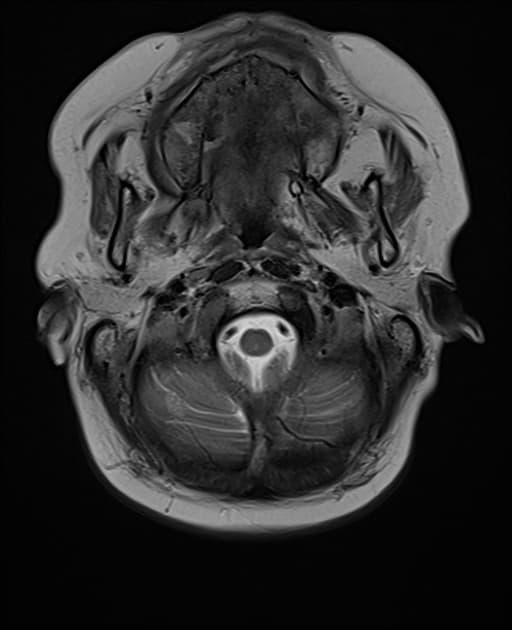

- Khối bắt thuốc dạng viền (ring-enhancing mass) ở thuỳ trán sau bên trái, kèm theo một lượng nhỏ phù vận mạch (vasogenic edema) xung quanh.

- Có một phần hạn chế khuếch tán (diffusion restriction) ở vùng ngoại vi, nhưng không có ở trung tâm.

Lesion "hoàn hảo" bắt thuốc dạng viền, nhưng không phải là áp xe não (do không có hạn chế khuếch tán ở trung tâm trên hình ảnh khuếch tán – DWI và lượng phù tương đối ít). MAGIC DR là từ viết tắt gợi nhớ hữu ích cho hình ảnh này.